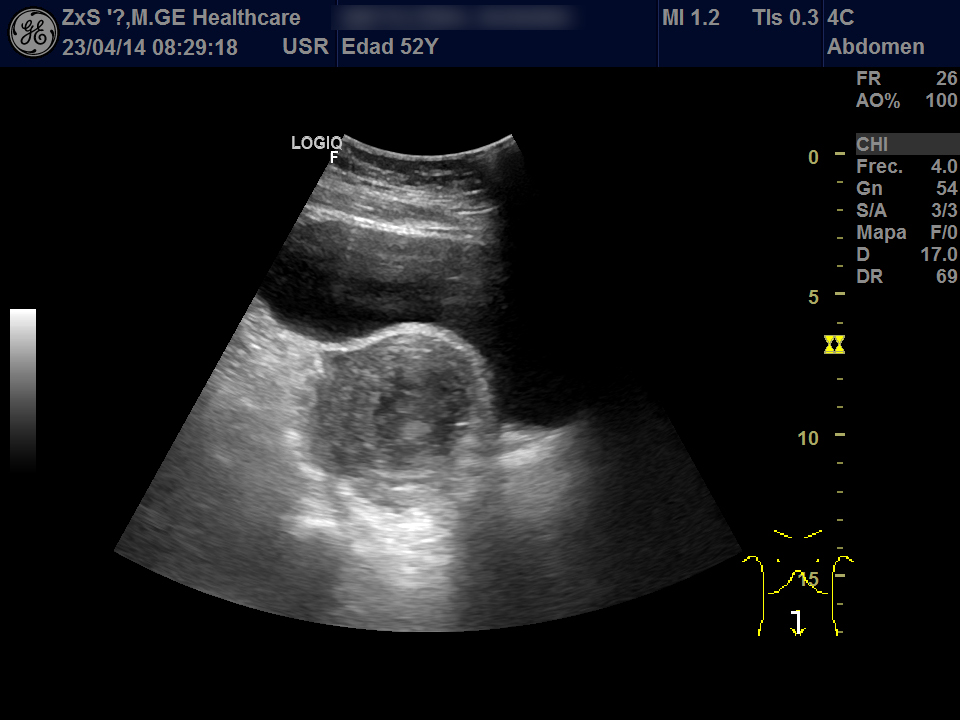

Hígado de bordes lisos y ángulo agudo, aspecto heterogéneo, no se observan LOES. Vía biliar extra e intrahepática no dilatada. Vesícula poco replecionada sin imágenes en su interior, Murphy ecográfico negativo. Ambos riñones de localización y tamaño normal. Buena diferenciación córtico-sinusal y en riñón derecho discreto aumento del tamaño de la pelvis renal compatible con hidronefrosis grado 2. Vejiga bien replecionada sin ecos en su interior. Se objetiva útero de tamaño normal con una imagen hiperecogénica que corresponde a DIU y en la zona derecha una lesión redondeada de aproximadamente 5,5 x 6,5 de diámetro de contenido heterogéneo que dudamos si puede corresponder a masa ovárica desconocida. Se deriva al hospital por sospecha de masa ovárica.

Evolución y seguimiento: Urgencias hospital TAC abdominal: en región anexial lesión de aspecto sólido-quístico de 6,5 x 5,5 cm con cambios inflamatorios de la grasa adyacente y que produce leve desplazamiento del útero hacia la izda. No se observan colecciones, neumoperitoneo, ni líquido libre intraabdominal.

Dco hospital: Absceso tubo-ovárico Ingreso. Se retira DIU y se pauta tto antibiótico IV. Posterior laparoscopia abierta: Plastrón inflamatorio que alberga trompa y anejo derecha íntimamente adherido a asas intestinales, útero y pared pélvica.